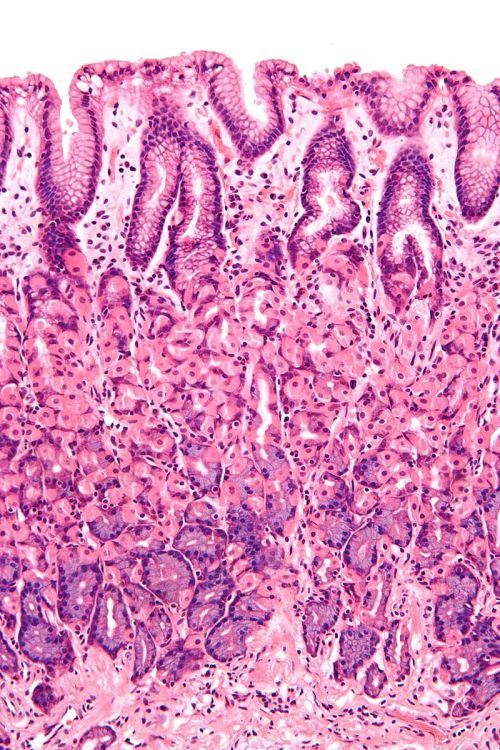

Pel que fa a la seva histologia, la paret del tub digestiu està format per quatre capes concèntriques que són de dins cap a fora:

- Capa interna o mucosa. És el revestiment interior del tub digestiu i es troba en contacte directe amb els aliments. Està composta per una capa d’epiteli, una capa de teixit conjuntiu que es diu làmina pròpia i una capa fina de múscul llis denominada muscularis mucosae. En l’epiteli hi poden haver glàndules que secreten diferents substàncies cap a la llum. Per exemple, les glàndules gàstriques situades a la mucosa de l’estómac secreten àcid clorhídric i pepsinogen per facilitar la digestió.

- Capa submucosa. Es troba sota la mucosa i està composta de teixit connectiu. Conté vasos sanguinis, glàndules i nervis que formen el plexe de Meissner, que és un component del sistema nerviós entèric amb la funció de controlar la motilitat de la mucosa i la funció secretora de les glàndules.

- Capa muscular externa, composta, de la mateixa manera que la muscularis mucosae, per una capa circular interna i una altra longitudinal externa de múscul llis (excepte a l’esòfag, on hi ha múscul estriat). Aquesta capa muscular té al seu càrrec els moviments peristàltics que desplacen el contingut de la llum al llarg del tub digestiu. Entre les seves dues capes hi ha un altre component del sistema nerviós entèric, el plexe mientèric d’Auerbach, que regula l’activitat d’aquesta capa.

- Capa serosa o adventícia. S’anomena segons la regió del tub digestiu que revesteix, és a dir, serosa si és intraperitoneal o adventícia si és retroperitoneal. L’adventícia està conformada per un teixit connectiu lax. La serosa apareix quan el tub digestiu ingressa a l’abdomen, i l’adventícia passa a ser substituïda pel peritoneu.

El gruix de la paret i l’aspecte de superfície, que pot ser llisa o no, canvien depenent del lloc anatòmic. La mucosa pot presentar criptes i vellositats, la submucosa pot presentar plecs permanents o plecs funcionals. A la paret hi ha també els plexes submucós i mientèric, que constitueixen el sistema nerviós entèric, que es distribueix al llarg de tot el tub digestiu, des de l’esòfag fins a l’anus.

A la figura podeu veure les diferents capes de l’aparell digestiu:

- Mucosa,

- Làmina pròpia de la mucosa

- Muscularis mucosae

- Lumen

- Teixit limfàtic

- Conducte de la glàndula

- Glàndula en mucosa

- Submucosa

- Glàndula a submucosa

- Plexe submucós de Meissner

- Vena

- Múscul circular

- Múscul longitudinal

- Teixit connectiu areolar

- Epiteli

- Plexe mientèric d’Auerbach

- Nervi

- Artèria

- Mesenteri